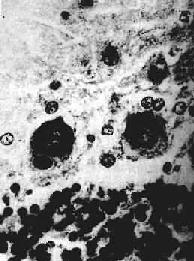

脑和脊髓充血明显,病变一般在神经根节、脑干下端、下丘脑等部位最为显著。镜下,可见弥漫性急性脑脊髓炎变化,有不同程度的神经元损害,从变性到坏死及神经细胞被吞噬;血管周围有淋巴细胞、浆细胞浸润,形成血管套。神经细胞内出现特征性的Negri小体具有病理诊断意义。该小体是神经细胞浆内的包含体,呈圆形或椭圆形,边界清楚,体积大,呈嗜酸性着色,多见于海马锥体细胞、小脑Purkinje细胞和大脑锥体细胞。每一神经细胞胞浆中小体的数目从一个到数个不等(图16-17)。炎症病变严重的部位,Negri小体数目往往不多。

狂犬病

图16-17 狂犬病

神经细胞胞浆中Negri小体